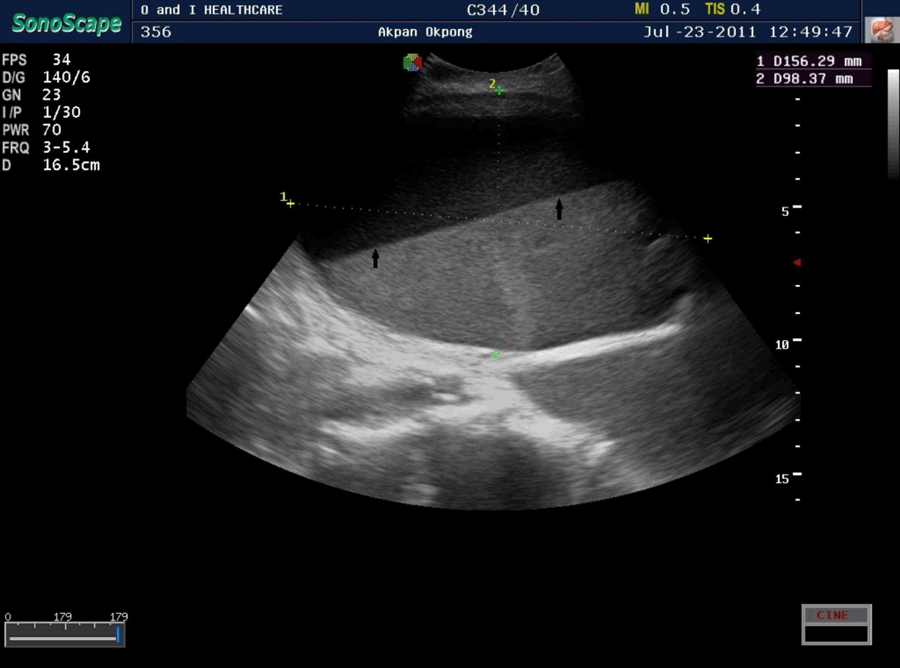

Clinical examination showed a weak, elderly man, with low body temperature (35°C), a respiratory rate of 30/min and an obtunded sensorium. There was bilateral pitting pedal oedema, generalized lower abdominal tenderness and the bladder size was 24 weeks. Abdomino-pelvic and transrectal ultrasonographic examination showed uniformly enlarged prostate (prostatic volume 85 cc) with no calcifications or suspicious foci, an enlarged bladder containing an estimated 1000 mL of fluid with fluid-fluid level, bilateral hydronephrosis and grade 3 renal parenchymal disease (Figures 1 and 2).

Figure 1: Ultrasound scan showed distended urinary bladder with fluid-fluid level (arrows).